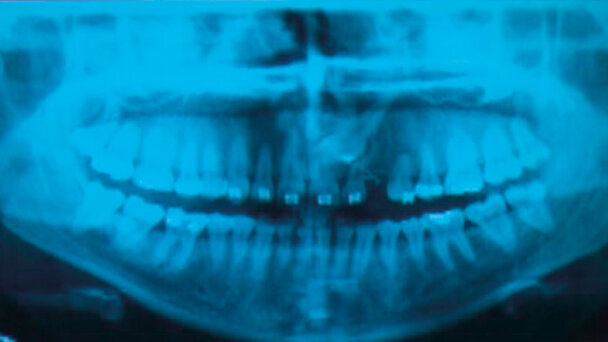

Nel 2007 si presenta alla nostra attenzione una paziente di sesso femminile, di anni 22, non fumatrice, in apparente buona salute sistemica. Durante la prima visita, analizzando l’OPT (Fig. 1) rileviamo il danno iatrogeno da terapia ortodontica precedente alla visita e riscontriamo la presenza del canino incluso in zona 23.

Abbiamo condiviso con la paziente la visione radiografica che metteva in evidenza come il canino si era impattato nella corticale ossea e dopo due anni e mezzo di terapia ortodontica fallimentare, riferita dalla stessa paziente, precedente al nostro intervento, la paziente ha preferito la proposta di estrarre il canino incluso 23 dell’arcata superiore e contemporaneamente inserire un impianto in zona.